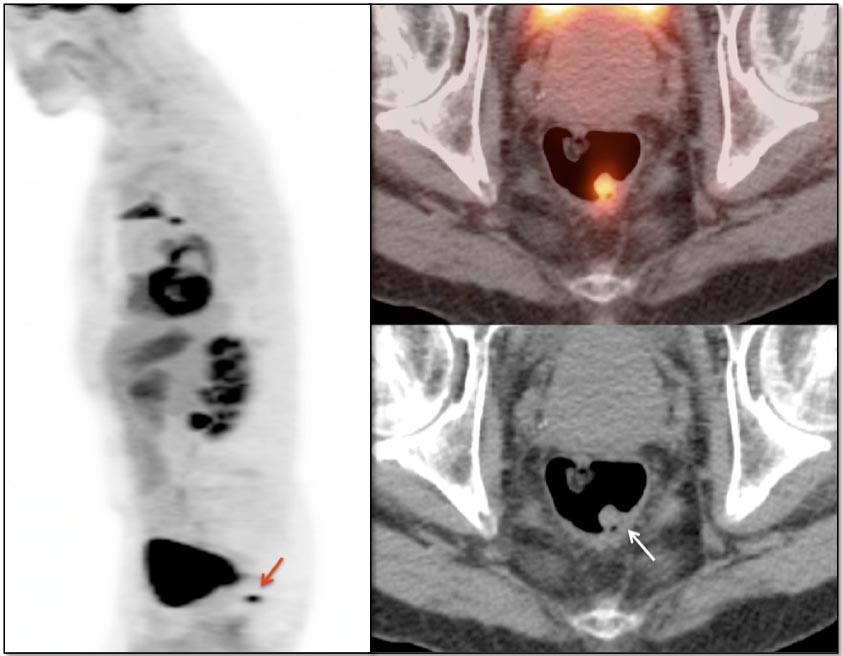

Focal intense uptake in the ano-rectal region is a very common finding. It is considered normal in the absence of an associated soft tissue abnormality. It is often attributed to hemorrhoidal inflammation.

Be careful to not confuse ano-rectal uptake (typically representing hemorrhoidal inflammation) with rectal uptake (often malignancy).